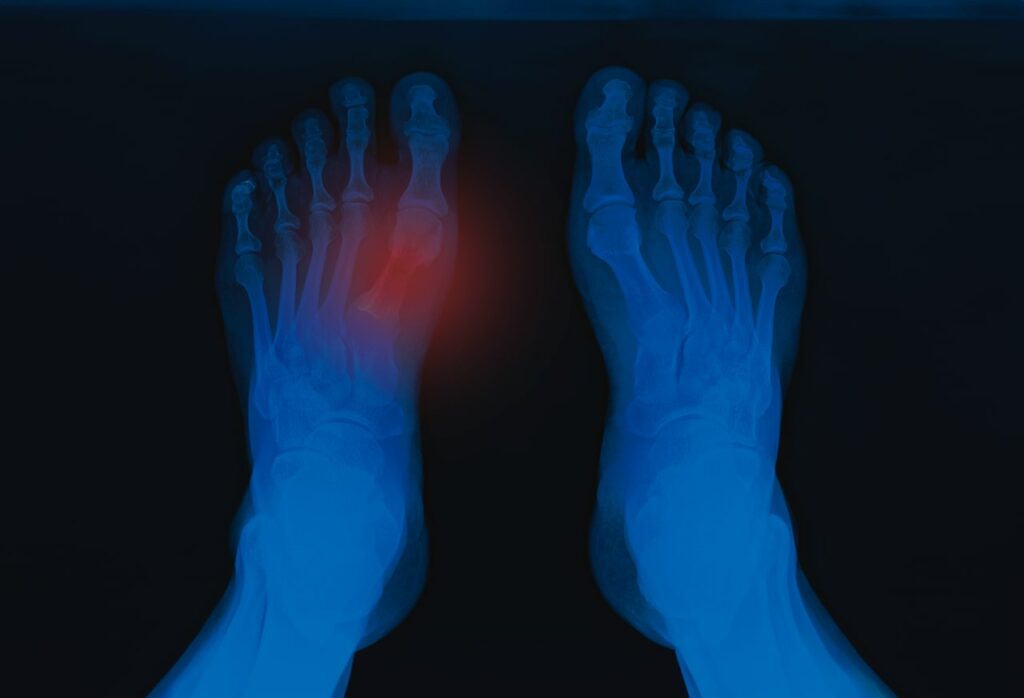

Radiografía de pies de una persona que presenta hiperuricemia y que ha desarrollado gota en uno de los dedos gordos de su pie

• Gota: es la manifestación clínica más conocida de la hiperuricemia y ocurre cuando los cristales de urato monosódico se depositan en las articulaciones generando inflamación y dolor intenso, es muy frecuente en el dedo gordo del pie, pero puede desarrollarse también en tobillos, rodillas, manos y codos.